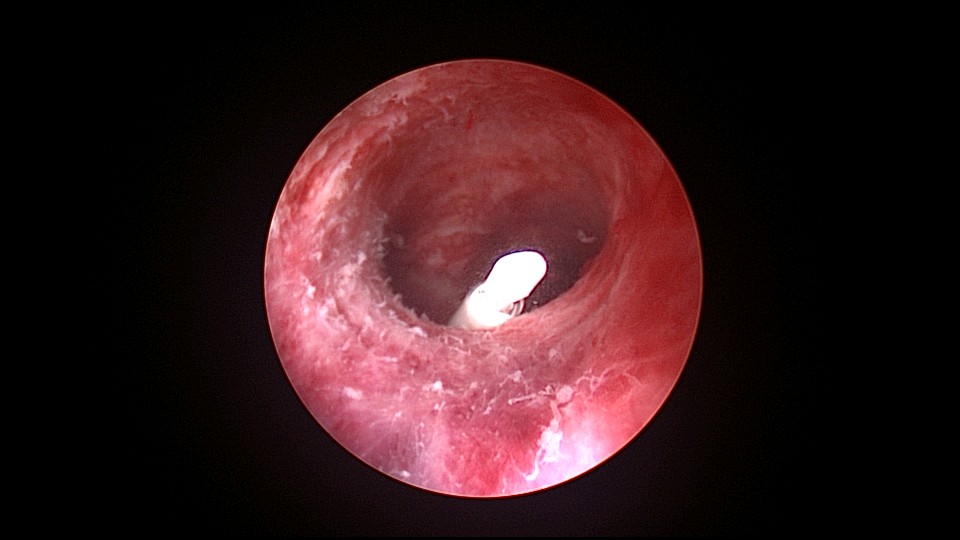

患者46岁,G2P2,顺产2次。因子宫腺肌症,严重痛经,8年前在江苏某医院放置曼月乐环,1+月后环脱落,未再继续治疗腺肌症,忍受了近7年痛经折磨。1+年前在外院再次放置曼月乐环,病人讲述手术医生做了环固定,最近月经量增多,痛经恢复至放环前,安环医院B超提示子宫后位,环已脱落,子宫7.4cm*7.4cm*8.4cm大小,朋友介绍到我院做曼月乐固定。宫腔镜见子宫后倾后屈位,宫深8.5cm,无法看到两侧宫角及子宫后壁,放弃缝合固定,用挂钩固定曼月乐环于宫底,先将不锈钢挂钩插入宫底肌层,4-0不可吸收线在曼月乐横臂中间套扎形成线圈,将曼月乐置入宫腔,异物钳夹持线圈挂到不锈钢挂钩里,原位固定曼月乐,退出宫腔镜,结束手术。术后多次复查B超,曼月乐位置正常,环顶端距宫底2.0cm。